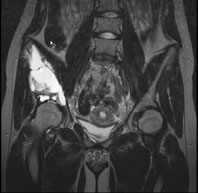

Ein 13-jähriges Mädchen kommt humpelnd zu Ihnen in die Praxis mit Schmerzen in der rechten Hüfte, die seit einigen Monaten bestehen und besonders bei Belastungen auftreten. Eine sichtbare Schwellung besteht nicht, kein Sturzgeschehen in der Anamnese.

Die Röntgenuntersuchung von Becken/Hüfte zeigt eine septierte geographische Osteolyse in der Ala und im Korpus des Os Iliums rechts. Das Röntgenbild und die Aufnahmen der nachfolgenden MRI-Untersuchung sehen Sie hier:

Becken/Hüfte pa

T2 FS, coronar, 5 mm